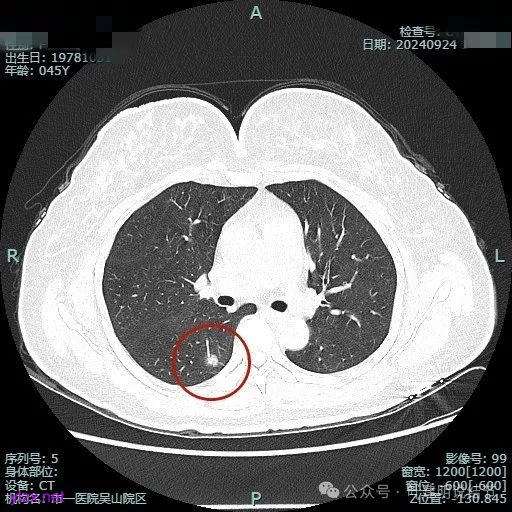

我们先来看2024年9月时的影像:

病灶1:

右下背段混合密度病灶,边上不太清爽,有片状淡磨玻璃影,实性部分密度较高。

感觉病灶有点晕征似的,表面不平,灶内不太致密。

有小血管进入,似有晕征。

离胸膜近但牵拉不明显,病灶边缘有细毛刺,较短且不太锐利。

边缘少许磨玻璃成分,血管进入明显。

瘤肺边界稍显不清。

病灶是混合密度,边缘少许淡磨玻璃,灶内不太致密,表面不平,血管征有,但说不上明显异常增粗。

病灶紧贴叶间裂,而且感觉跨过肺叶,部分影响到上叶了,病灶本身密度虽实性为主,但是不太致密,有点松散的感觉。

总体实性部分密度较高,而磨玻璃部分密度较低,且瘤肺边界欠清,关键是跨叶间裂生长,这与肿瘤似乎不容易解释些。

毛刺有但不太锐利,磨玻璃有但偏淡,实性为但不太致密,叶间裂与之关系密切,病灶跨叶生长。

上图显得与肿瘤较为符合,但跨叶生长的话,侵袭力应该较强,可她这病灶较刚发现时进展并不太明显。

上图层面也较符合恶性,血管进入明显,有浅分叶的样子,整体觉得有一定收缩力与膨胀感。

病灶表面不平,混合密度,磨玻璃成分较淡。